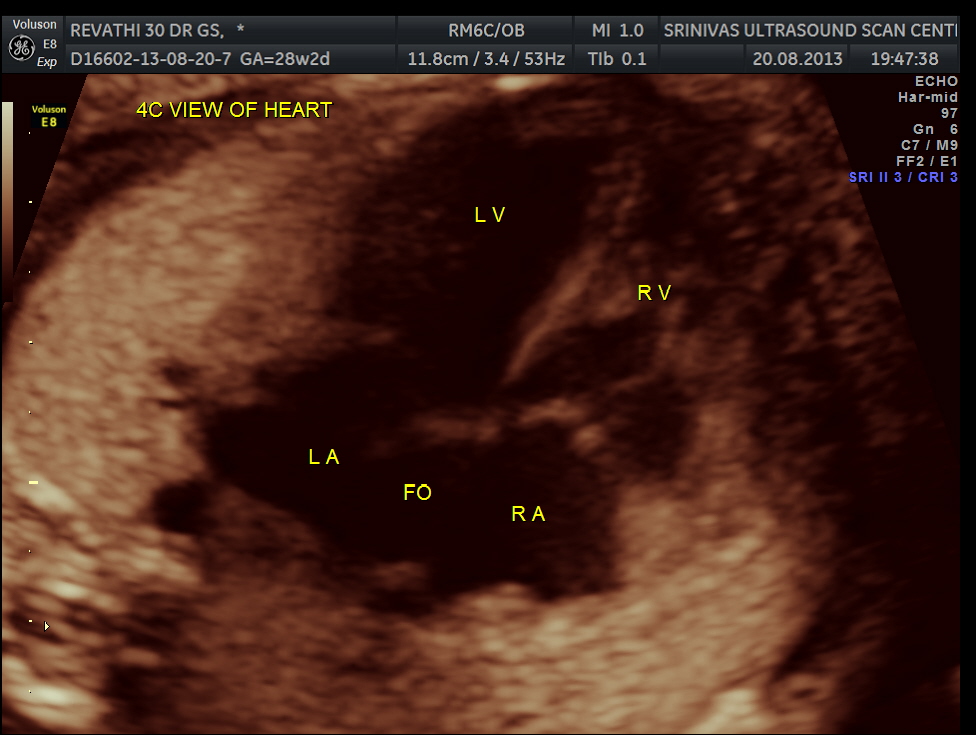

4 chamber view is given below .

The cardiac axis appeared to be abnormal .